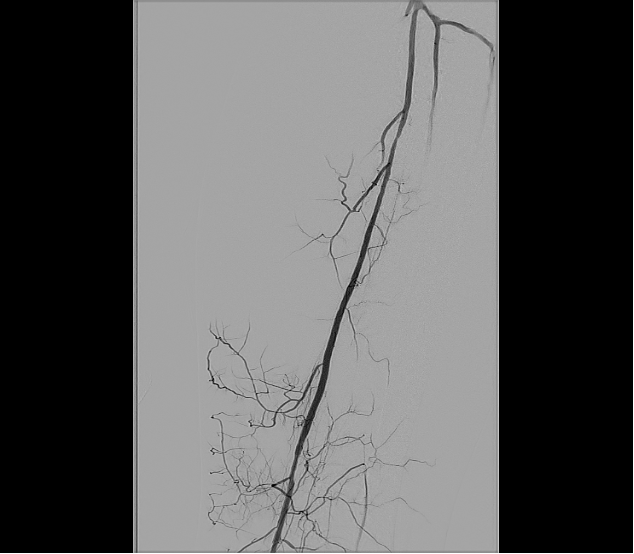

Based on his comorbidities, history of recurrent stenting of the left SFA, and an occlusion of the SFA over 200 cm, he was deemed to be an appropriate candidate for percutaneous transmural arterial bypass (PTAB). However, in order to establish long-term patency, we proceeded to gain posterior tibial artery access to identify a 3-vessel runoff (Figure 2). With this information, using the outline of the stents in left SFA and using a 0.018-in Glidewire Advantage (Terumo) and a 0.018-in Rubicon catheter (Boston Scientific), we were able to obtain access into the left profunda femoral artery (Figure 3). Despite multiple-balloon angioplasty, the recoil within the left common femoral artery (CFA) left little option but to place a 7.0-mm Eluvia stent (Boston Scientific), which was overlapped with the proximal stent in the left SFA (the profunda femoral artery was patent after balloon angioplasty; Figure 4).